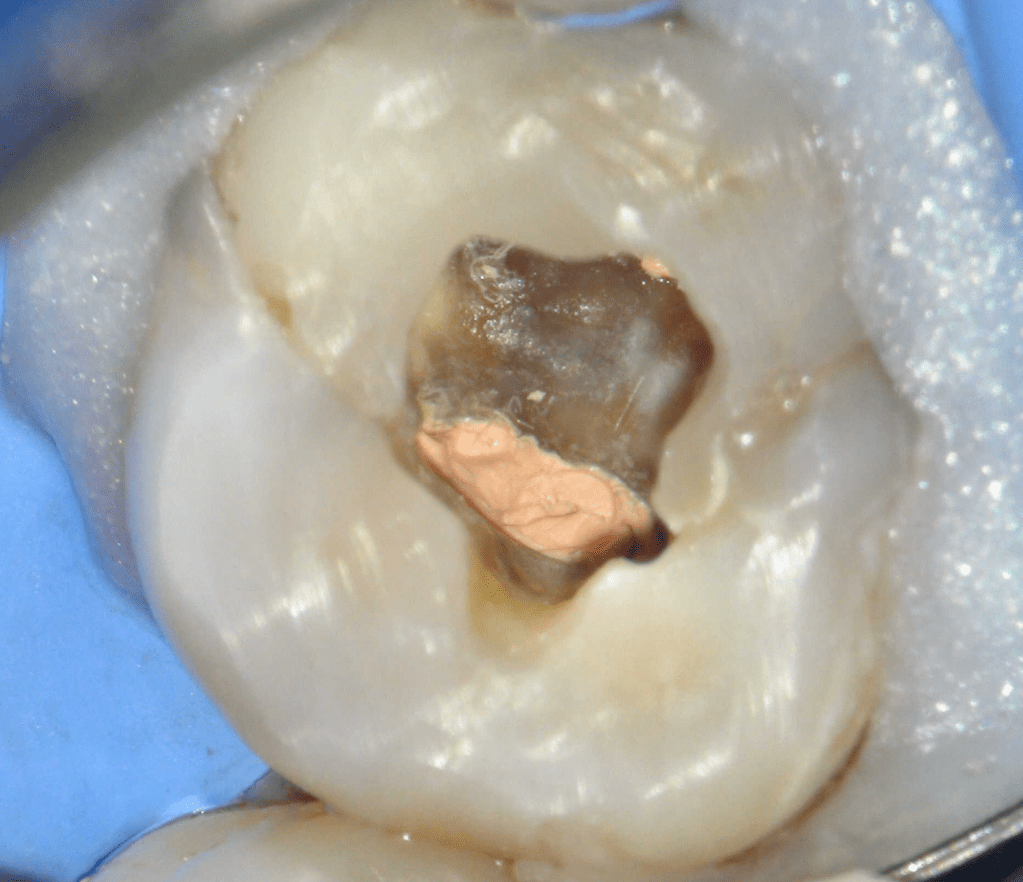

Molar superior